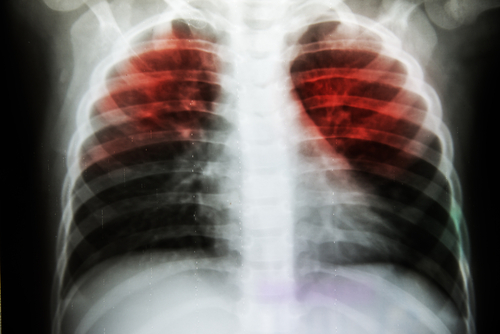

Tuberculosis has long been a problem which has plagued the nation. The World Health Organisation (WHO) estimated that around 2.79 million cases of TB were detected in India in 2016 alone. A recent study published in the Lancet Journal of Infectious Diseases questions whether the most commonly used methods of testing for TB are effective enough to diagnose the issue on such a large scale. Experts in India, however, seem divided on this.

According to the latest study published in the Lancet journal, which was conducted by researchers in the United Kingdom, the current methods of testing might need to be updated. The study notes that these methods might not be fast enough to pick up positive diagnoses which would be ideal in a country like India where a large population may be at risk of TB exposure. In India, a delay of a few days could have a significant impact on the overall presentation of tuberculosis in the country, according to several experts.